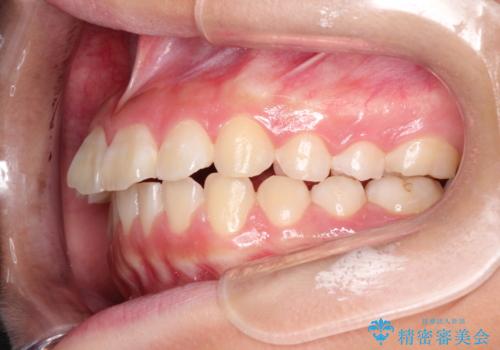

- 前歯が出ているのを主訴に来院されました。

上の前歯が前方に傾斜しており、上の前歯と下の前歯が接触していない状態でした。

上の奥歯を後方に移動させて、前歯を引っ込める計画としました。